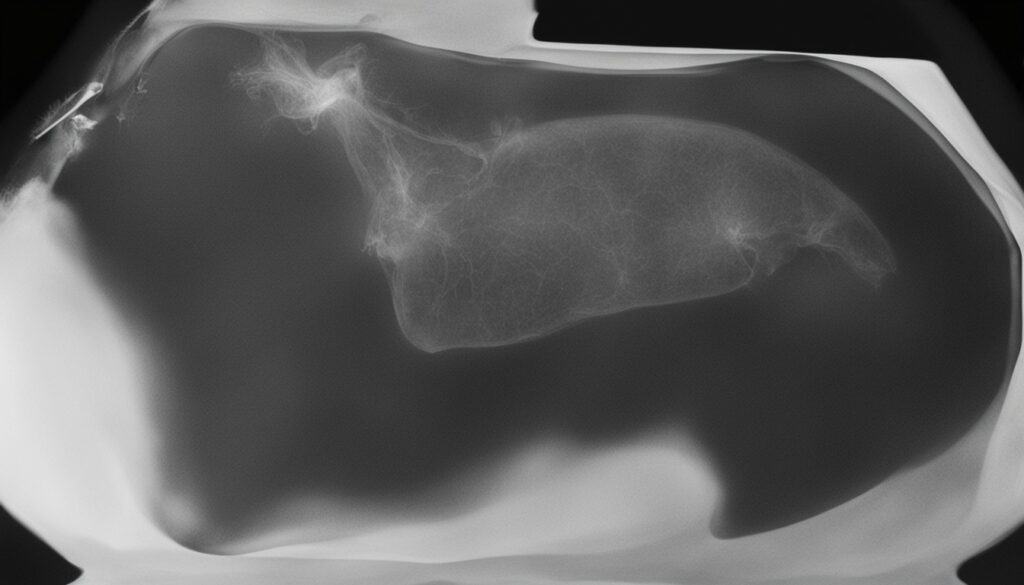

Tools like X-rays and ultrasounds help look at the adrenal glands2. They show if there’s a tumor there, which could be causing Cushing’s disease.

X-rays and Abdominal Ultrasound Visualize adrenal glands and assess organ abnormalities

Source 1 Imaging techniques such as X-rays and abdominal ultrasound are valuable tools for diagnosing Cushing’s disease in dogs and assessing the size and presence of tumors.2